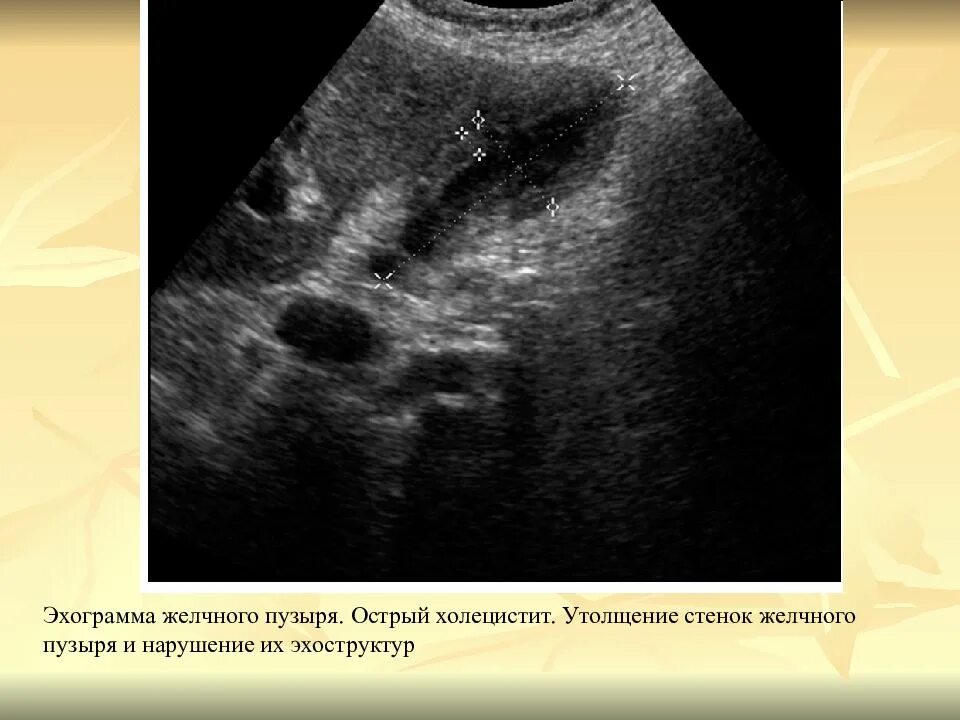

Диффузные изменения стенок желчного пузыря